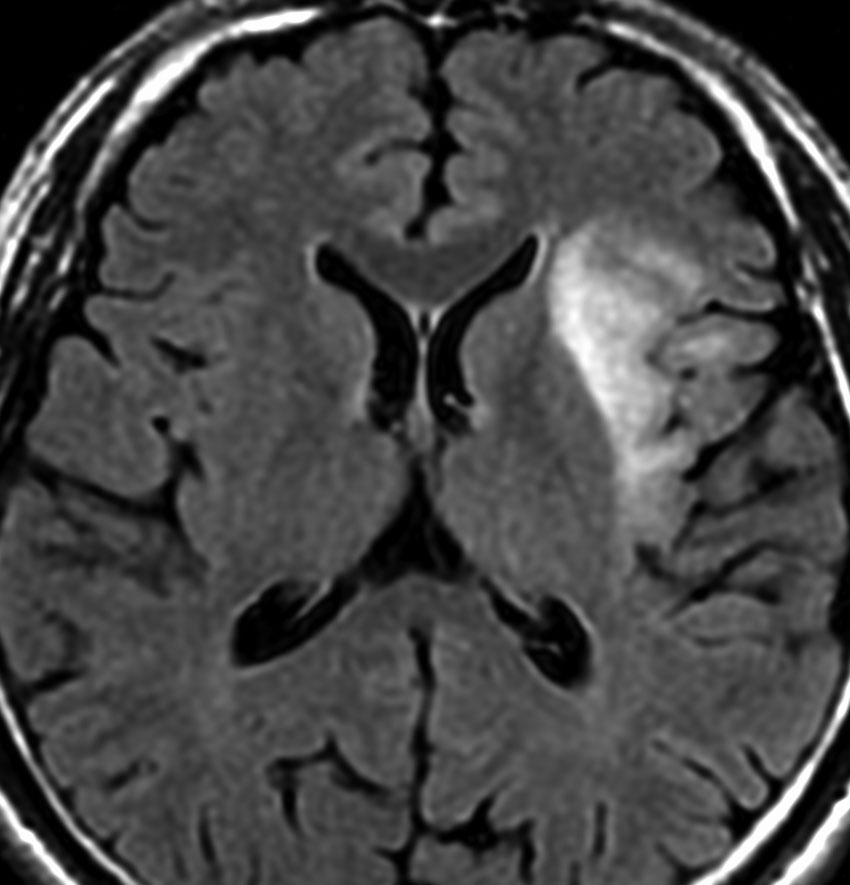

左の画像は放射線治療直後のMRIですが,すでに腫瘍の縮小がみられます。

テモゾロマイドの維持療法は,24コース 2年間行い,それ以降は無治療としました。

照射後7年の画像です。腫瘍は縮小したまま,患者さんは無症状で経過しています。